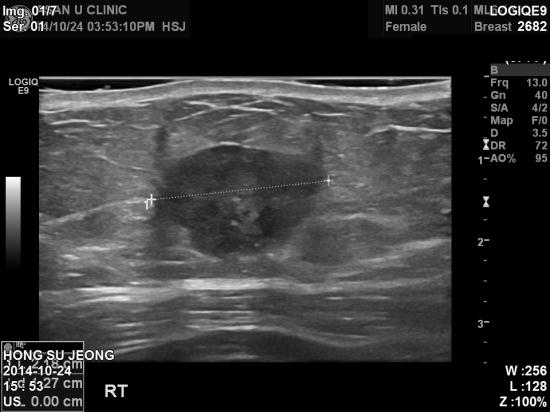

갑자기 오른쪽 가슴에 만져지는 혹이 있어 내원한 67세 여성분입니다.

유방 초음파상 2.1cm정도의 혹이 있었고

겨드랑이 림프절은 비대됨없어

유방의 혹만 조직검사했으며

침윤성 유관암으로 진단되었습니다.